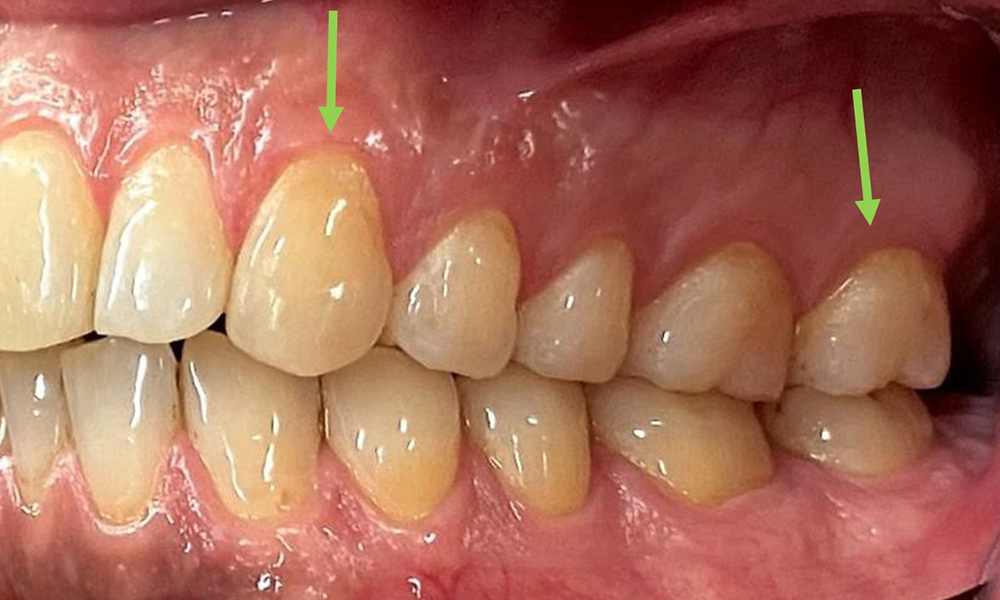

The patient has full dentition with a total of 28 teeth. There were noteworthy erosions and attritions. (Fig. 4, Fig. 5). Due to bruxism, the patient has been wearing a splint with an adjusted bite block at night for many years. The erosions were caused by long-term consumption of isotonic beverages. No periodontal bone loss or active caries were observed.

At 1 to 3 mm, the clinical probing depths were within the physiological range. Maxillary recessions of up to 1 mm were observed from 13 to 16 and 23 to 27. The BOP was 15%.

Full complement of adult teeth with no caries or radiologically recognizable bone loss was observed (Fig. 6). Radiological enamel and cusp loss were particularly evident on 36 and 37.